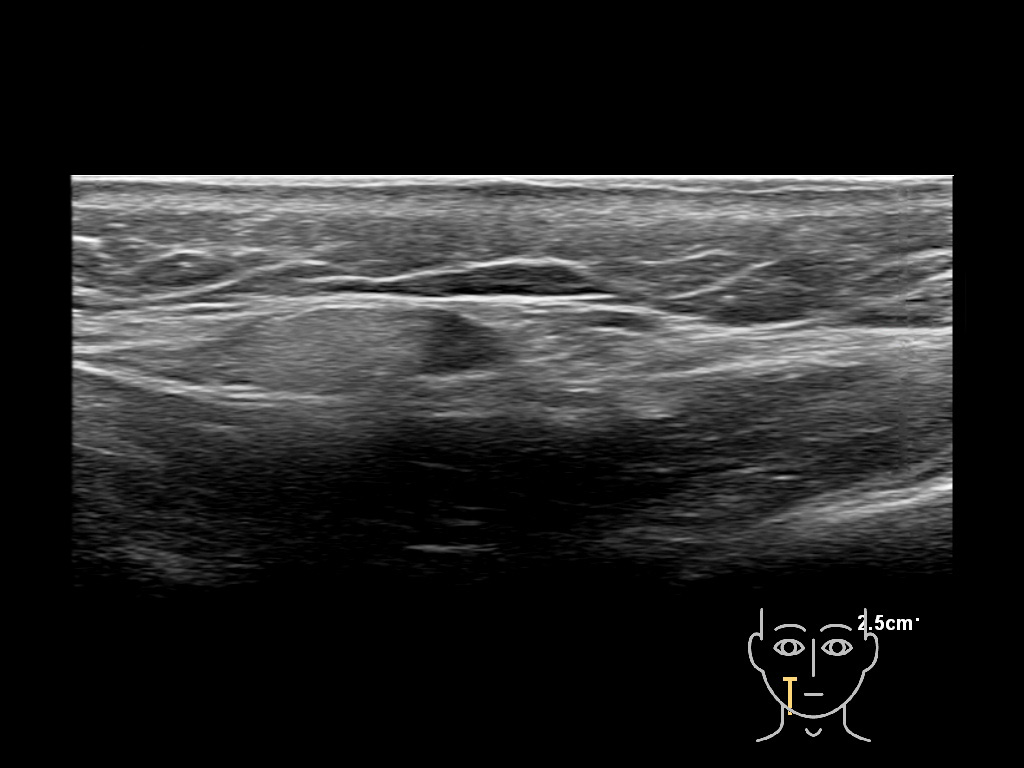

Filler injections in the parotid gland may go unnoticed, however, inflammatory reactions and abscesses may occur. Hypervascularity can be seen with color doppler. Filler deposits are supposed to be injected into the superficial fatty layer . The space to inject into this layer may be limited. Routinely we measure a width of 2-4 millimeters with sometimes subcutaneous layers being less than one millimeter thick.

Study the first image to recognize the different layers. If you are sure about the layers, swipe to the second image to view the answer (if applicable).